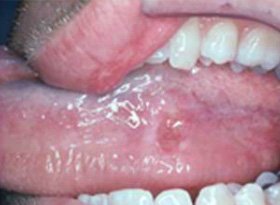

Oral cancer occurs when abnormal cells develop in the lips, tongue, gums, cheek lining, or floor of the mouth. If left untreated, these cells may grow and spread to other areas. Therefore, early screening becomes extremely important.

Oral Cancer

- White or red patches inside the mouth